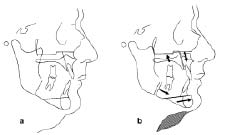

Immediate Custom Implant Provisonalization: A Prosthetic Technique

Surgical and restorative techniques that can reduce the loss of hard and soft tissues are desirable. The use of a custom fabricated provisional will provide a mechanism by which preservation of hard and soft tissue can be achieved. This article will explore two different scenarios where the fabrication of an immediate custom provisional and provisional … Read more